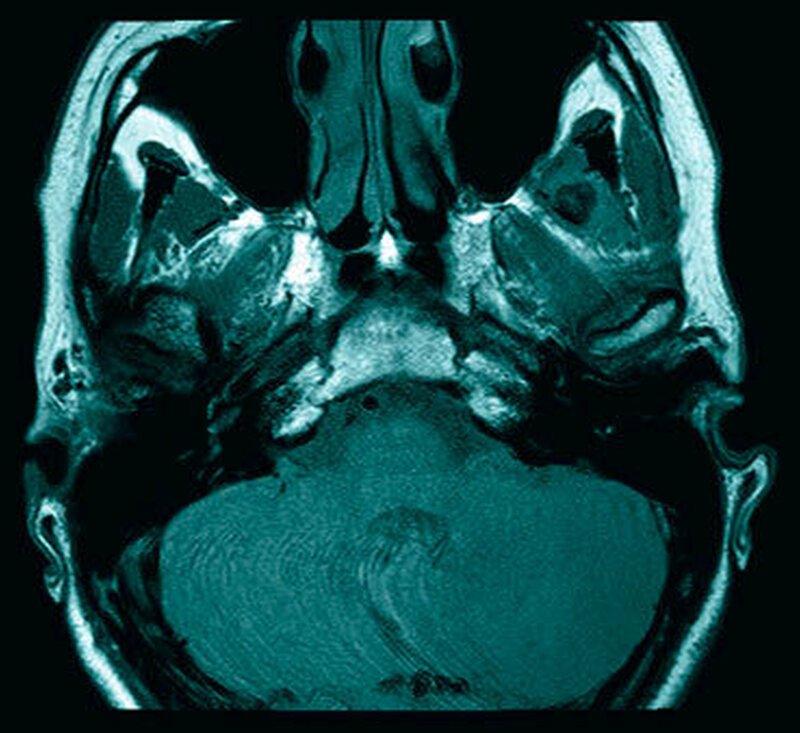

Das neun Tage später durchgeführte MRT zeigte keinen Anhalt für eine Läsion des Diskuskomplexes beidseits. Es wurde jedoch eine umschriebene, teils T2-hyperintense sowie kräftig randständig kontrastmittelaufnehmende Läsion im M. pterygoideus medialis links (axial bis zirka 1,0 cm) angrenzend an den Processus muscularis vereinbar mit einem kleinen intramuskulären Abszess beschrieben (Abbildungen 2 a und b). Des Weiteren erschien der M. pterygoideus medialis links in seinem ganzen Verlauf ödematös verändert, jedoch ohne Anhalt für eine Beteiligung der umliegenden Strukturen wie dem M. pterygoideus lateralis.